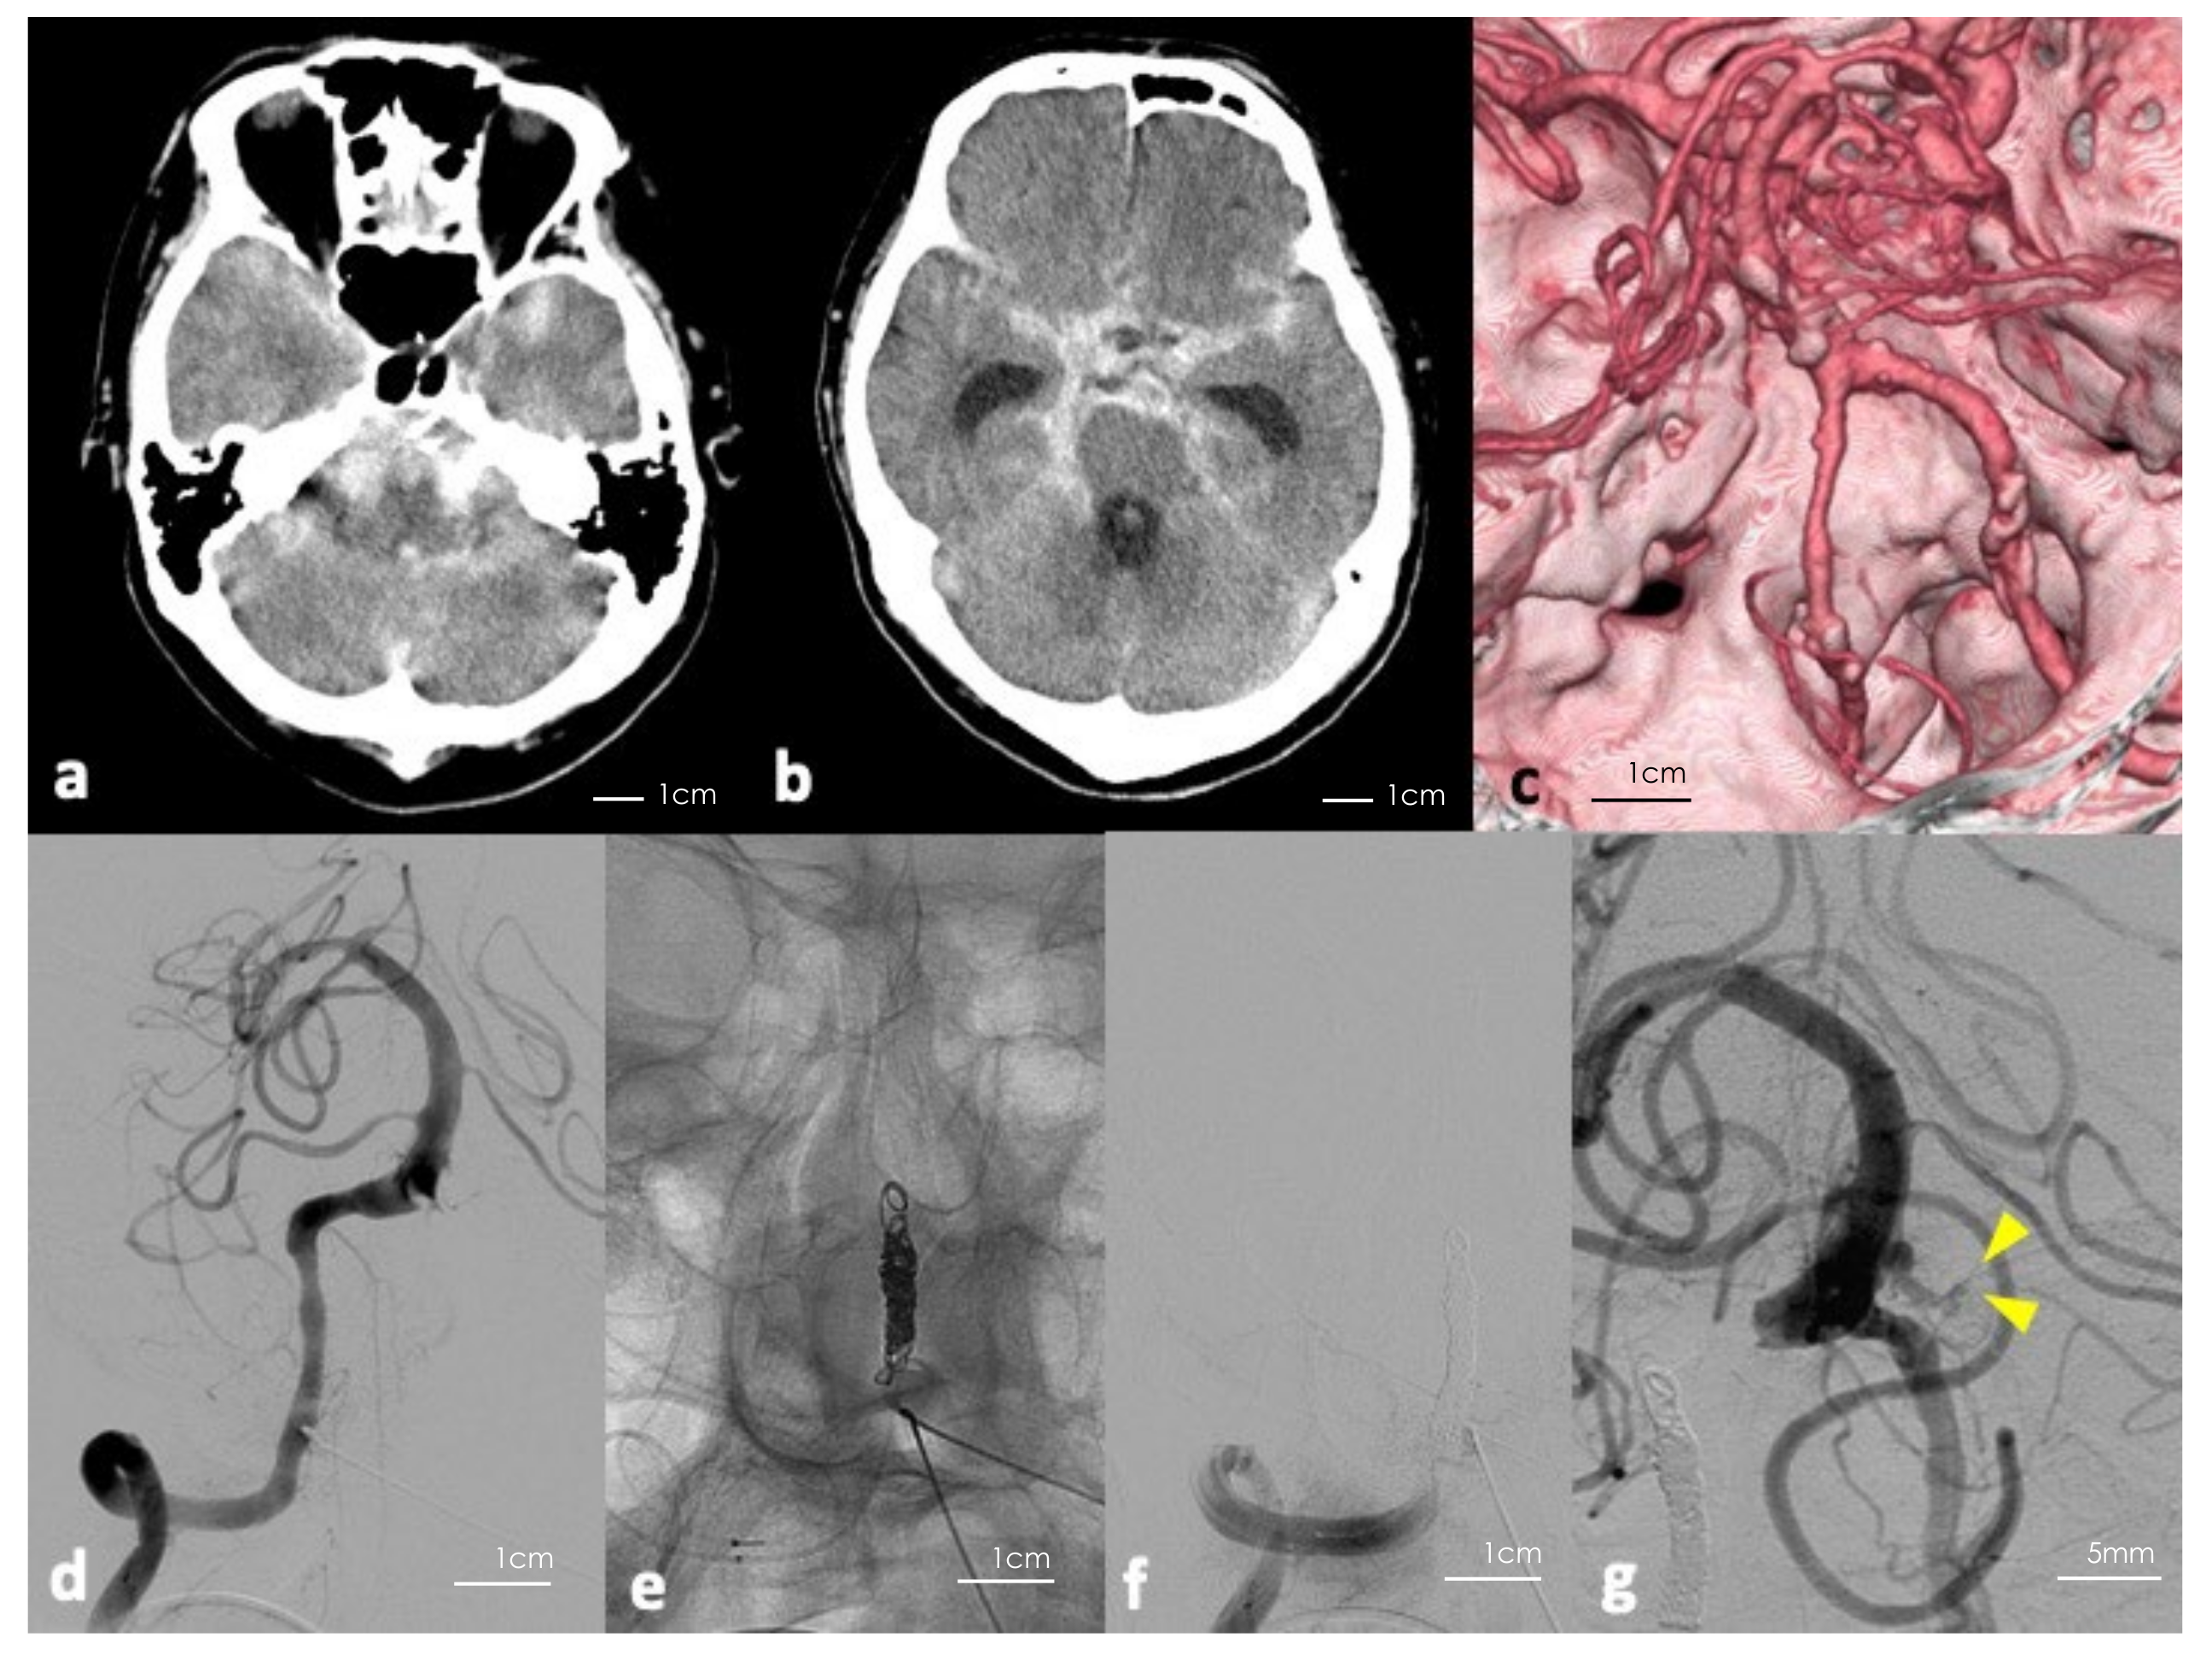

Figure 1.

(a,b) Initial computerized tomography (CT) of the head showing massive subarachnoid hemorrhage. (c) Three-dimension reconstructed CT angiography of the head showing no apparent saccular aneurysm. (d–f) Digital subtraction angiography (DSA) of the right vertebral artery before and after parental artery occlusion using coils. (g) Follow-up DSA showing blood flow in the aneurysm including the bleb (yellow arrowheads indicating the bleb).

Based on Figure 1c, from the distribution of the hematoma and findings on DSA, we assumed that the rupture point could be caused by the dissection of the right VA. Thus, we performed a parent artery embolization (Figure 1d–f). However, follow-up DSA revealed a previously undetected partially thrombosed saccular aneurysm at the vertebrobasilar junction or the lower section basilar trunk (Figure 1g). The neck was 2.4 mm × 2.2 mm, the aneurysmal dome was approximately 8 mm × 6 mm × 6 mm, and the lumen was 4 mm in a longitudinal direction. To prevent re-rupture of the aneurysm, we performed microsurgical clipping and wrapping. Following parent artery embolization, the patient’s mental status recovered to GCS 14 points, but deteriorated gradually due to hydrocephalus. His preoperative GCS was 8 points and modified Rankin Scale (mRS) score was 5.